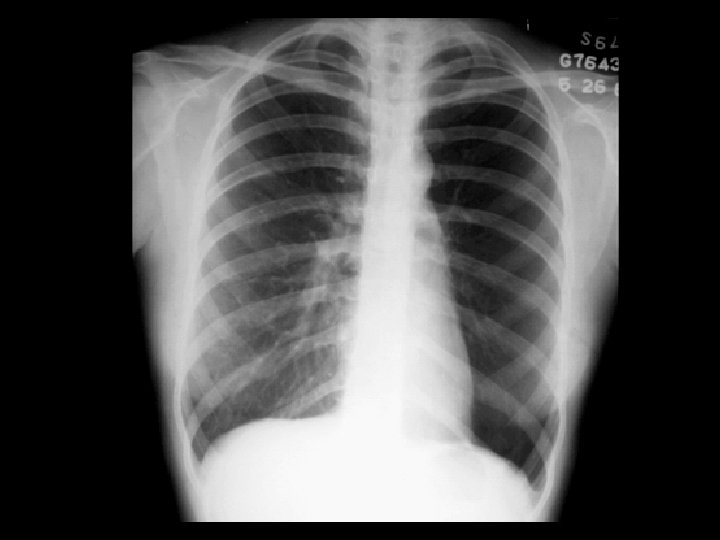

RUL collapse • Findings: – Wedge-shaped opacity of the right apex – Upper displacement of the minor fissure – Right sided mediastinal shift – Elevation of the right hemidiaphragm • ddx: – NONE! – This is an Aunt Minnie!